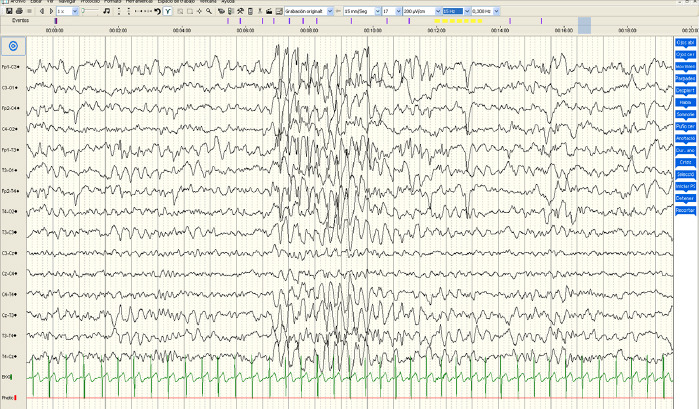

Introduction: Angelman syndrome is a genetic disorder characterised by severe mental retardation, subtle dysmorphic facial features, a characteristic behavioural phenotype, seizures and abnormalities in video electroencephalograms (video EEG). Angelman syndrome may be associated with genetic mechanisms involving the region of chromosome 15q11-13. Up to 90% of cases have epileptic seizures, usually in the early years of life. Videoelectroencephalography patterns with some typical characteristics associated with Angelman syndrome have been reported, although these are not specific to it, and as such it is also useful for early diagnosis, especially in the first months or years of life.

Patients and methods: We conducted a retrospective observational study of 34 video EEGs performed on 17 patients diagnosed with Angelman syndrome at the clinical neurophysiology service of the Puerta de Hierro University Hospital in Madrid between 2019 and 2022. The primary objective was to characterise the videoelectroencephalographic findings and compare them with previously published studies. As secondary objectives, we analysed the patterns proposed by Dan and Boyd, and other demographic, genetic and clinical data.

Results: Video EEG supported the clinical suspicion in our study, as baseline brain activity was altered in all the patients. We identified a pattern similar to those defined by Dan and Boyd in 88% of the cases, and the type III pattern was the most common in our series.